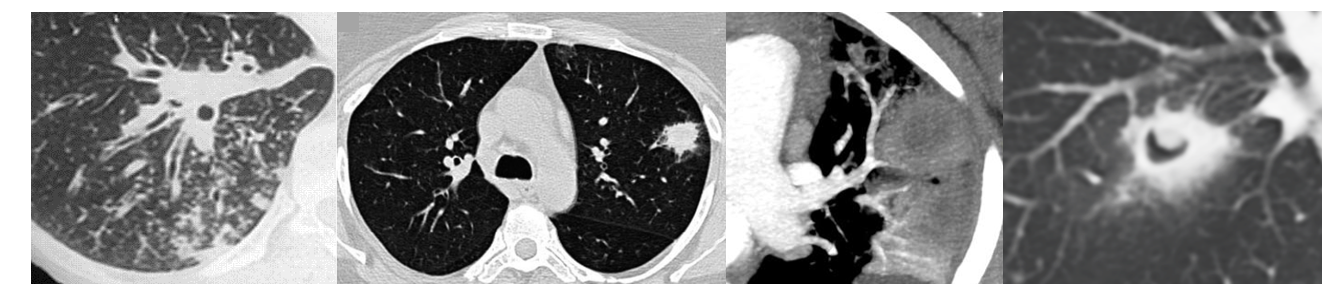

5.7.1 Imaging

CT Findings Suggestive of IPA:

- Nodules with halo sign (ground-glass surrounding dense core)

- Air-crescent sign (late finding with neutrophil recovery)

- Wedge-shaped infiltrates

- Cavitation

The halo sign (ground-glass attenuation surrounding a nodule) is relatively specific for angioinvasive mold infection in neutropenic patients, particularly in the first week of infection.

CT Pulmonary Angiography (Vessel Occlusion Sign):

- Can help differentiate IPA from other pulmonary processes

- Positive VOS shows vessel truncation within or adjacent to nodules

- CT findings: Centrilobular nodules, tree-in-bud pattern

| 0-3 | Hyphal tissue invasion | Macronodule ± halo sign | GM may be negative |

| 5-7 | Hemorrhage, infarction | Dense consolidation | Serum GM positive |

| 10-12 | Extensive necrosis | Hypodense sign | High fungal burden |

| 15-18 | Neutrophil recovery, cavitation | Air-crescent sign | May persist |